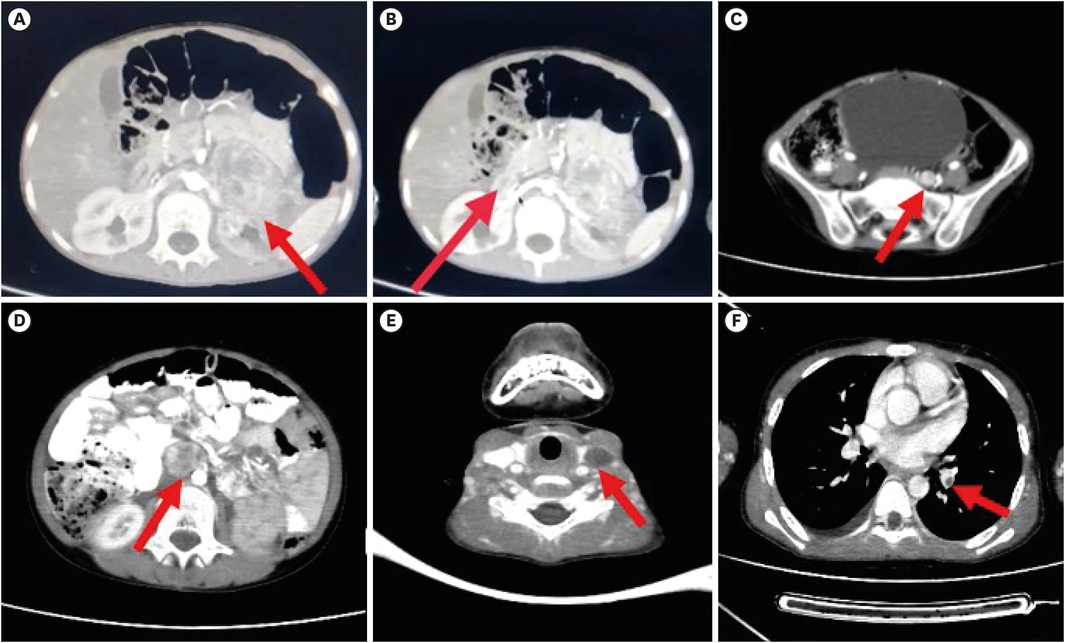

A 13 years boy presented in our emergency room with altered sensorium, hypertensive crisis, peripheral ischemia and breathlessness. Patient was in his usual state of health till 9 years of age. Then he started having symptoms of pain in left lower abdomen, nausea, vomiting and headache. He was diagnosed with hypertension and was started on antihypertensives by a physician. After an uneventful period of about 4 years with intermittent episodes of headache, excessive sweating and pain abdomen patient developed chest pain and dyspnea. During this episode echocardiography showed a decreased left ventricular ejection fraction (LVEF) of 20%. Two weeks back patient developed features of acute abdomen with blackening of fingers and toes (Fig. 1 and B) along with altered sensorium and visited us. His blood pressure (BP) was very high (210/120 mmHg) and heart rate was 180 per minute. Classical history of headache, palpitations and sweating along with hyper-enhancing mass on contrast enhanced computed tomography (CECT) suggested the diagnosis of PPGL syndrome. There was no history of any similar kind of illness in any other family member. He was admitted in intensive care unit and emergent hypertensive crisis management was started. Patient was started on alpha blocker—prazosin 5 mg once daily and gradually increased to 25 mg per day, nifedipine 10 mg twice daily per day. Beta blocker (Metoprolol 150 mg daily) was added after 5 days of alpha blocker therapy. With this his symptoms subsided and peripheral ischemia resolved. His further evaluation revealed very high plasma free normetanephrine (4,668 pg/mL), normal plasma free metanephrine (46 pg/mL), normal serum calcitonin (2 pg/mL) and normal serum calcium (8.4 mg/dL). Triple phase CECT abdomen showed hyper-enhancing tumors at left suprarenal, right perihilar, inter-aortocaval and organ of Zuckerkandl locations (Fig. 2A-D). CECT done for screening of von Hippel Lindau syndrome revealed left IJV thrombosis and thrombosis of segmental branches of left pulmonary artery (Fig. 2E and F).

Fig. 2

CECT abdomen axial images showing (A) enhancing mass in left suprarenal location extending anterior to left kidney (arrow). (B) Another enhancing lesion noted at right renal hilum (arrow). (C) Enhancing lesion noted anterior to left sacral ala adjacent to left iliac vessels (arrow). (D) Enhancing mass noted in inter-aortocaval location (arrow). (E) Axial CECT neck showing left IJV thrombosis (arrow). (F) Axial CECT thorax showing thrombosis in segmental branch of lift pulmonary artery (arrow).

CECT, contrast enhanced computed tomography; IJV, internal jugular vein.